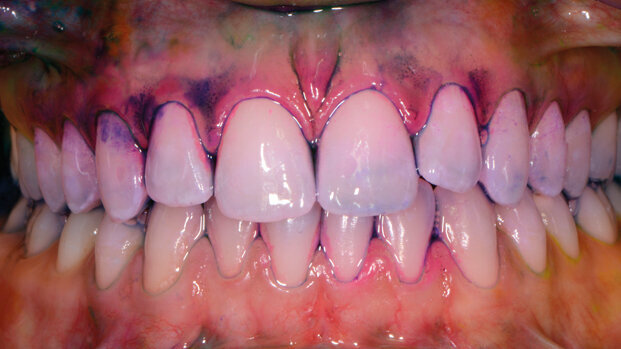

Un corretto protocollo domiciliare di gestione del biofilm orale è indispensabile per mantenere lo stato di salute del cavo orale (Fig. 1), sia esso primario sia per terapia di mantenimento in seguito a cure odontoiatriche. In particolare, la rimozione meccanica della placca tramite le manovre di igiene orale domiciliare può prevenire l’insorgenza o rendere reversibile una condizione di gengivite (Van der Weijden, 2005).